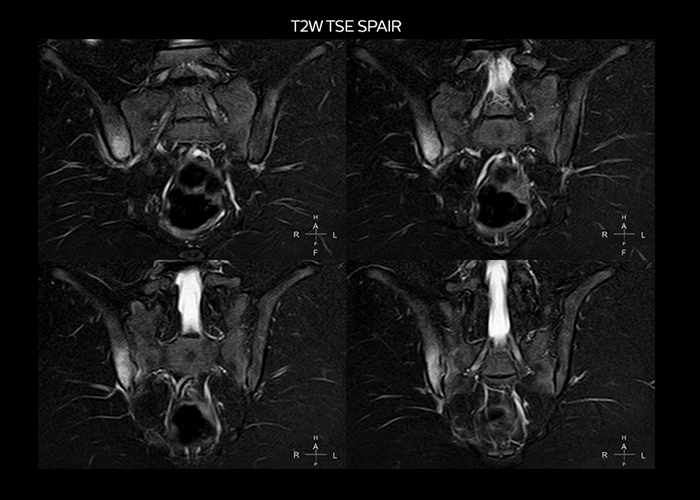

“On average, we scan about 80 patients per day, but on some days we scan well over 100 patients. The scanner is in use 7 days per week, operated 20 hours per day on week days and 8 hours per day in the weekend,” Mr. Tuna says. “To avoid coil changes we plan examinations of similar anatomies back to back, such as head and spine. Multiva helps us here a lot because coils don’t need to be changed frequently. Moreover, thanks to parallel imaging technology and 16-channel HeadSpineTorso and 8-channel MSK coils we are able to achieve excellent image quality. In this way Multiva helped us to increase both image quality and productivity.” “Neurological cases, such as brain and spine imaging, represent the largest share in our MR scanning, followed by musculoskeletal cases. In general, we use simple and basic imaging protocols. But occasionally, we use advanced techniques for problematic cases if necessary.